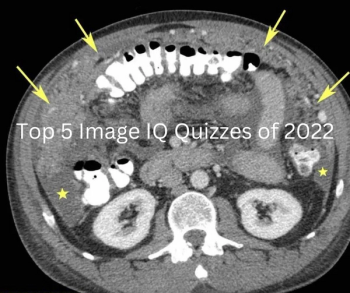

Catch up on the most well-read Image IQ quizzes from 2022.